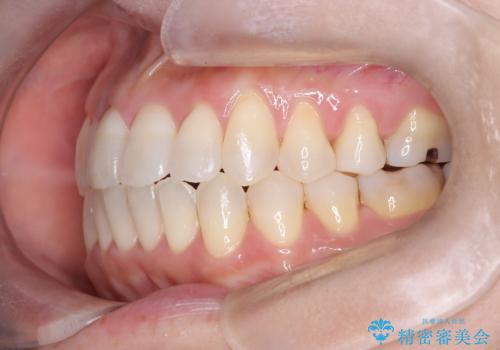

【開咬】笑った時の見た目を改善したい。

- 重度の開咬でしたがインビザラインで適切に治療計画を立て、きれいに仕上がりました。